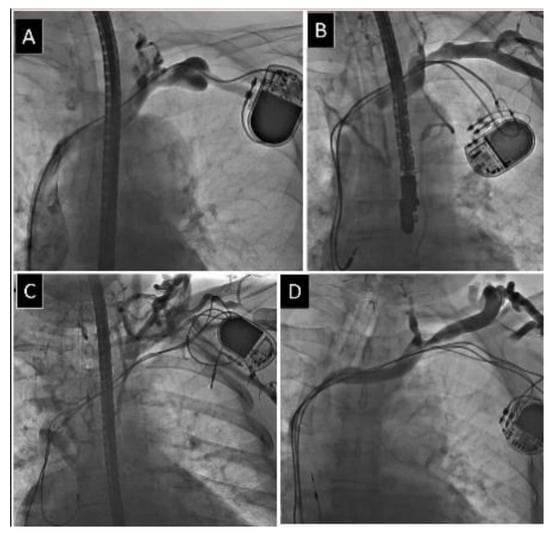

2.2. Venography